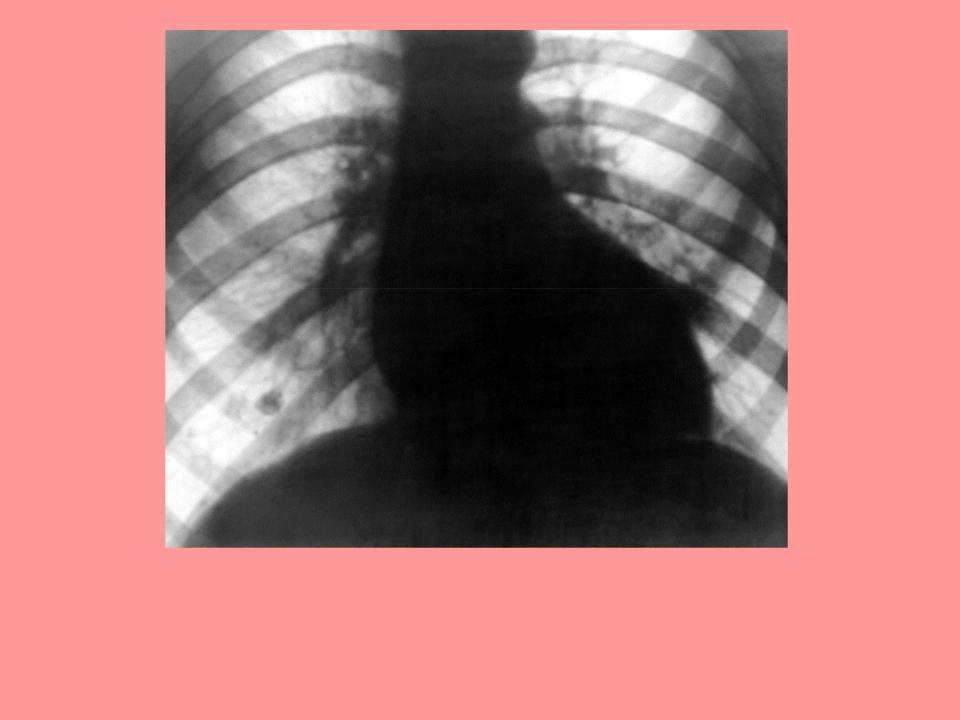

Рентгенограмма грудной клетки больного с аортальным стенозом: поперечник сердечной тени увеличен влево, талия сердца резко выражена, дуга левого желудочка удлинена и закруглена («аортальная» конфигурация).